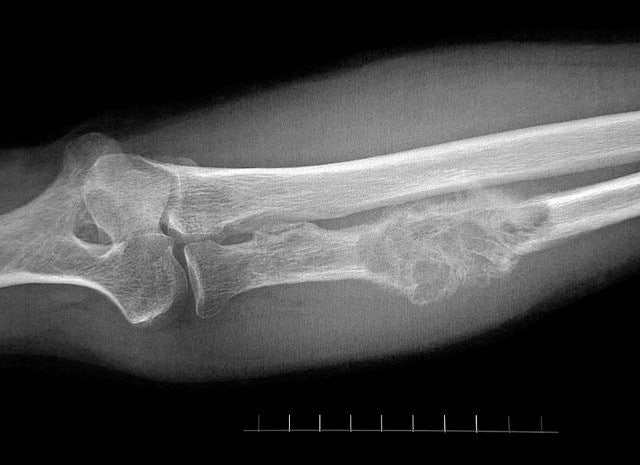

골종양은 크게 연골종양, 골종양, 전이성 종양 및 기타 골종양으로 나뉜다. 연골종양 중 연골종은 연골세포로 구성된 비교적 흔한 양성종양으로 내연골종과 외연골종으로 나눌 수 있다. 주로 젊은 사람들에게 발생하며 다발성이며 일반적으로 손가락과 발가락의 뼈에서 발견됩니다.

이 밖에도 골연골종(osteochondroma)과 골연골육종(osteochondrosarcoma)이 있는데, 골연골육종은 겨드랑이 연골 종양을 말하며 주로 견갑골, 갈비뼈, 엉덩이뼈에 발생하며 악성 골암의 20%를 차지하며 대부분 중년 이후에 발생한다. 골암은 골암에 비해 골종(osteoma)과 골육종(osteosarcoma)으로 나뉘는데 골종은 골조직의 종양으로 비교적 드문 단일 양성 종양으로 가드너 증후군이나 가족력에 의해 발생하며 전형적인 악성 골종양이다. 모든 뼈 종양의 약 10%에서 출혈과 괴사를 동반합니다. 어떤 경우에는 골 파괴 또는 불규칙한 골 형성 경향이 명백합니다. 전이성 종양은 뼈 이외의 상피 조직에서 발생합니다. 악성 종양이 전이되어 혈액과 골수에 종양을 형성한 경우입니다. 뼈로 전이되기 쉬운 종양에는 유방암, 전립선암, 갑상선암 및 폐암이 포함됩니다.